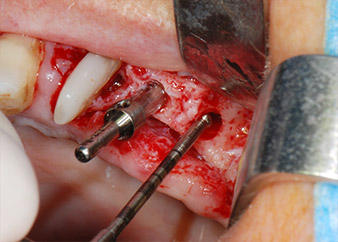

Les lits implantaires ont été préparés sur les sites 25 et 26 à l'aide d'instruments rotatifs, utilisés dans un contre-angle avec un rapport de transmission 20:1 avec un nouveau moteur d'implantologie puissant (Implantmed, W&H) (Fig. 8).

Les implants (Restore, Keystone Dental, 3,75 mm de diamètre, 8,0 mm de long) ont été mis en place à l'aide du moteur d'implantologie (Fig. 11 et 12).